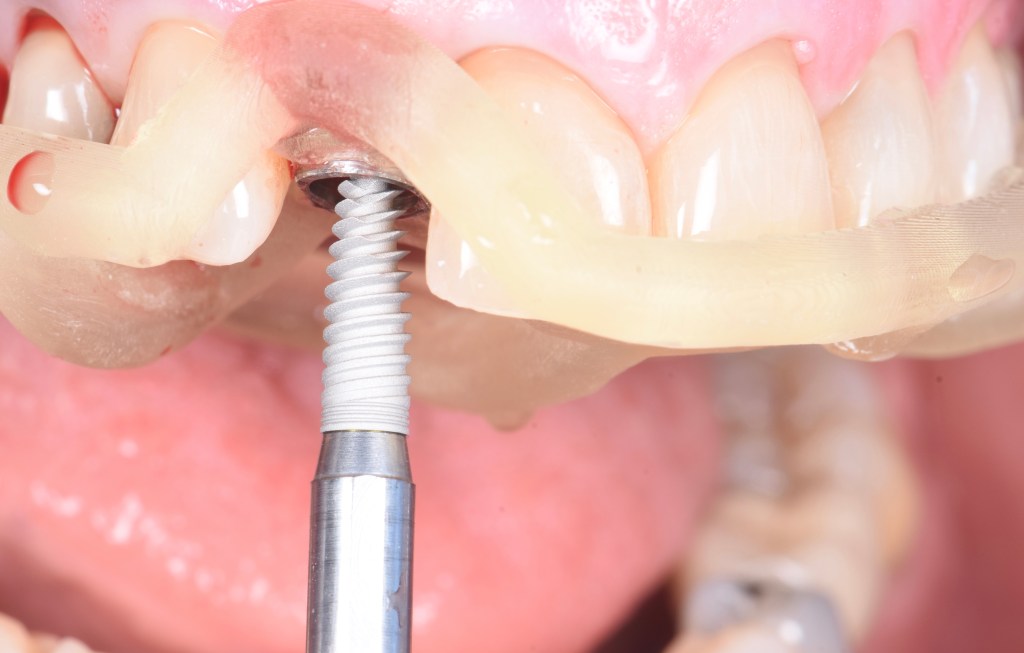

Chirurgie guidée implantaire

Il est primordial d’utiliser un guide chirurgical afin d’avoir une émergence implantaire situé derrière a l’endroit adéquat. C’est un outil primordial dans notre pratique, afin de sécuriser l’acte chirurgical et d’éviter un positionnement « a main levée ». La planification et la confection sont réalisées au sein du cabinet, au laboratoire de prothèse

Après une analyse esthétique, fonctionnelle et radiologique complète, nous avons pu réaliser les extractions des dents non conservables, la mise en place des implants ainsi que la réalisation d’un bridge provisoire immédiat. Des guides chirurgicaux ont été utilisés afin d’augmenter la précision de l’acte chirurgical. 3 mois après, un bridge complet en céramique Zircone a été réalisé

Ici, cette patiente présentait une absence totale de dents du haut compensé par un appareil dentaire complet. Après une planification rigoureuse impliquant des radiographies 3D, scanner, photographies, nous avons pu prévoir sur une matinée la pose de 6 implants à travers un guide chirurgical, ainsi que la mise en place d’un bridge provisoire complet. La patiente est donc repartie avec des dents fixes. 3 mois après, le bridge définitif a pu être réalisée en céramique polycristalline (Zircone)